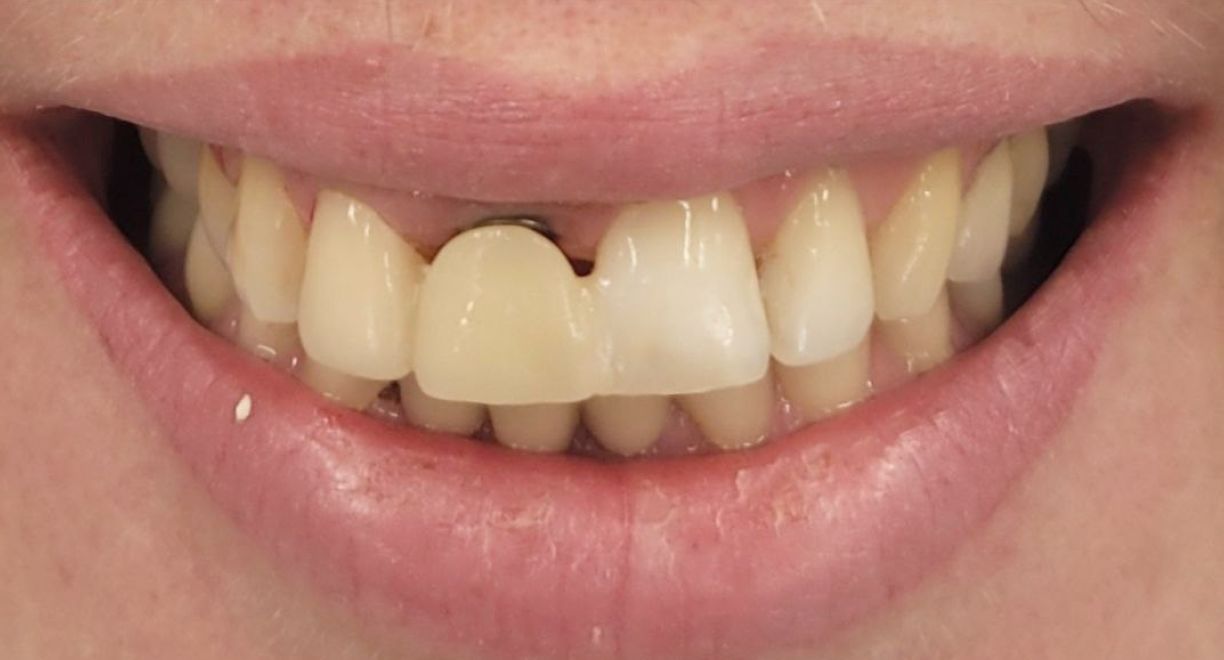

• Single-Tooth Dental Implant Placement + Dental Veneers for Full Smile Aesthetics

The patient was missing one tooth, and based on a detailed clinical evaluation, an individualized treatment plan was created. A titanium dental implant was placed into the jawbone, functioning as an artificial tooth root and providing a stable foundation for long-term restoration. After complete osseointegration, a custom-made zirconia crown was fabricated. It accurately replicates the natural tooth’s color, shape, and anatomy, restoring both chewing function and aesthetics. The neighbouring teeth are not affected during the treatment and remain intact. To ensure full smile aesthetics and a harmonious final result, dental veneers were also placed for the patient.